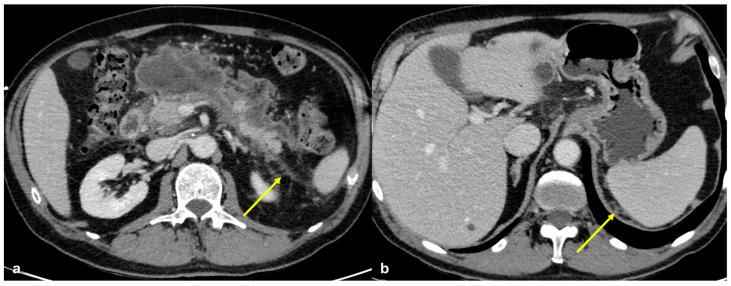

The peritoneum is a thin membrane that lines the abdominal cavity and covers the abdominal organs. It serves as a conduit for the spread of various pathological processes, including gas and fluid collections, inflammation, infections, and neoplastic conditions. Peritoneal carcinomatosis is the most common and well-known pathology involving the peritoneum, typically resulting from the dissemination of gastrointestinal and pelvic malignancies. However, numerous benign and malignant peritoneal diseases can mimic the imaging appearance of peritoneal carcinomatosis. The aim of this review is to revisit the anatomy of peritoneal compartments and elucidate the patterns of peritoneal disease spread. Emphasis is placed on identifying the distinctive imaging features of both neoplastic and non-neoplastic peritoneal diseases that differ from peritoneal carcinomatosis.

腹膜是一层薄的膜,它衬于腹腔内并覆盖腹部器官。它是各种病理过程扩散的通道,包括气体和液体聚集、炎症、感染及肿瘤性疾病。腹膜癌病是涉及腹膜的最常见且广为人知的病理情况,通常由胃肠道和盆腔恶性肿瘤的播散引起。然而,许多良性和恶性腹膜疾病可模仿腹膜癌病的影像学表现。本综述的目的是重新审视腹膜腔室的解剖结构并阐明腹膜疾病的扩散模式。重点在于识别与腹膜癌病不同的肿瘤性和非肿瘤性腹膜疾病的独特影像学特征。